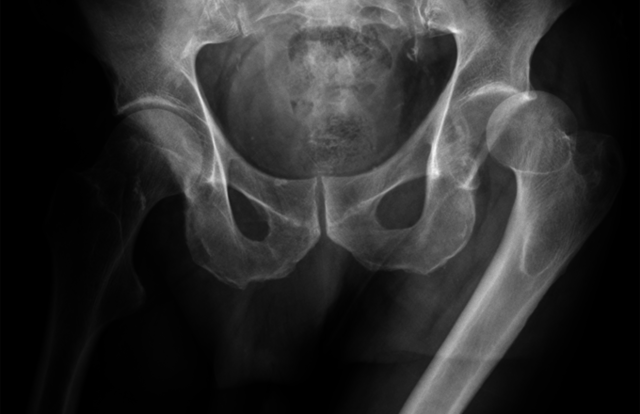

Hip dislocation

When I was 1 year and started walking my family saw my problem.

After discovering the dislocation , the doctors had to have surgery a few days later